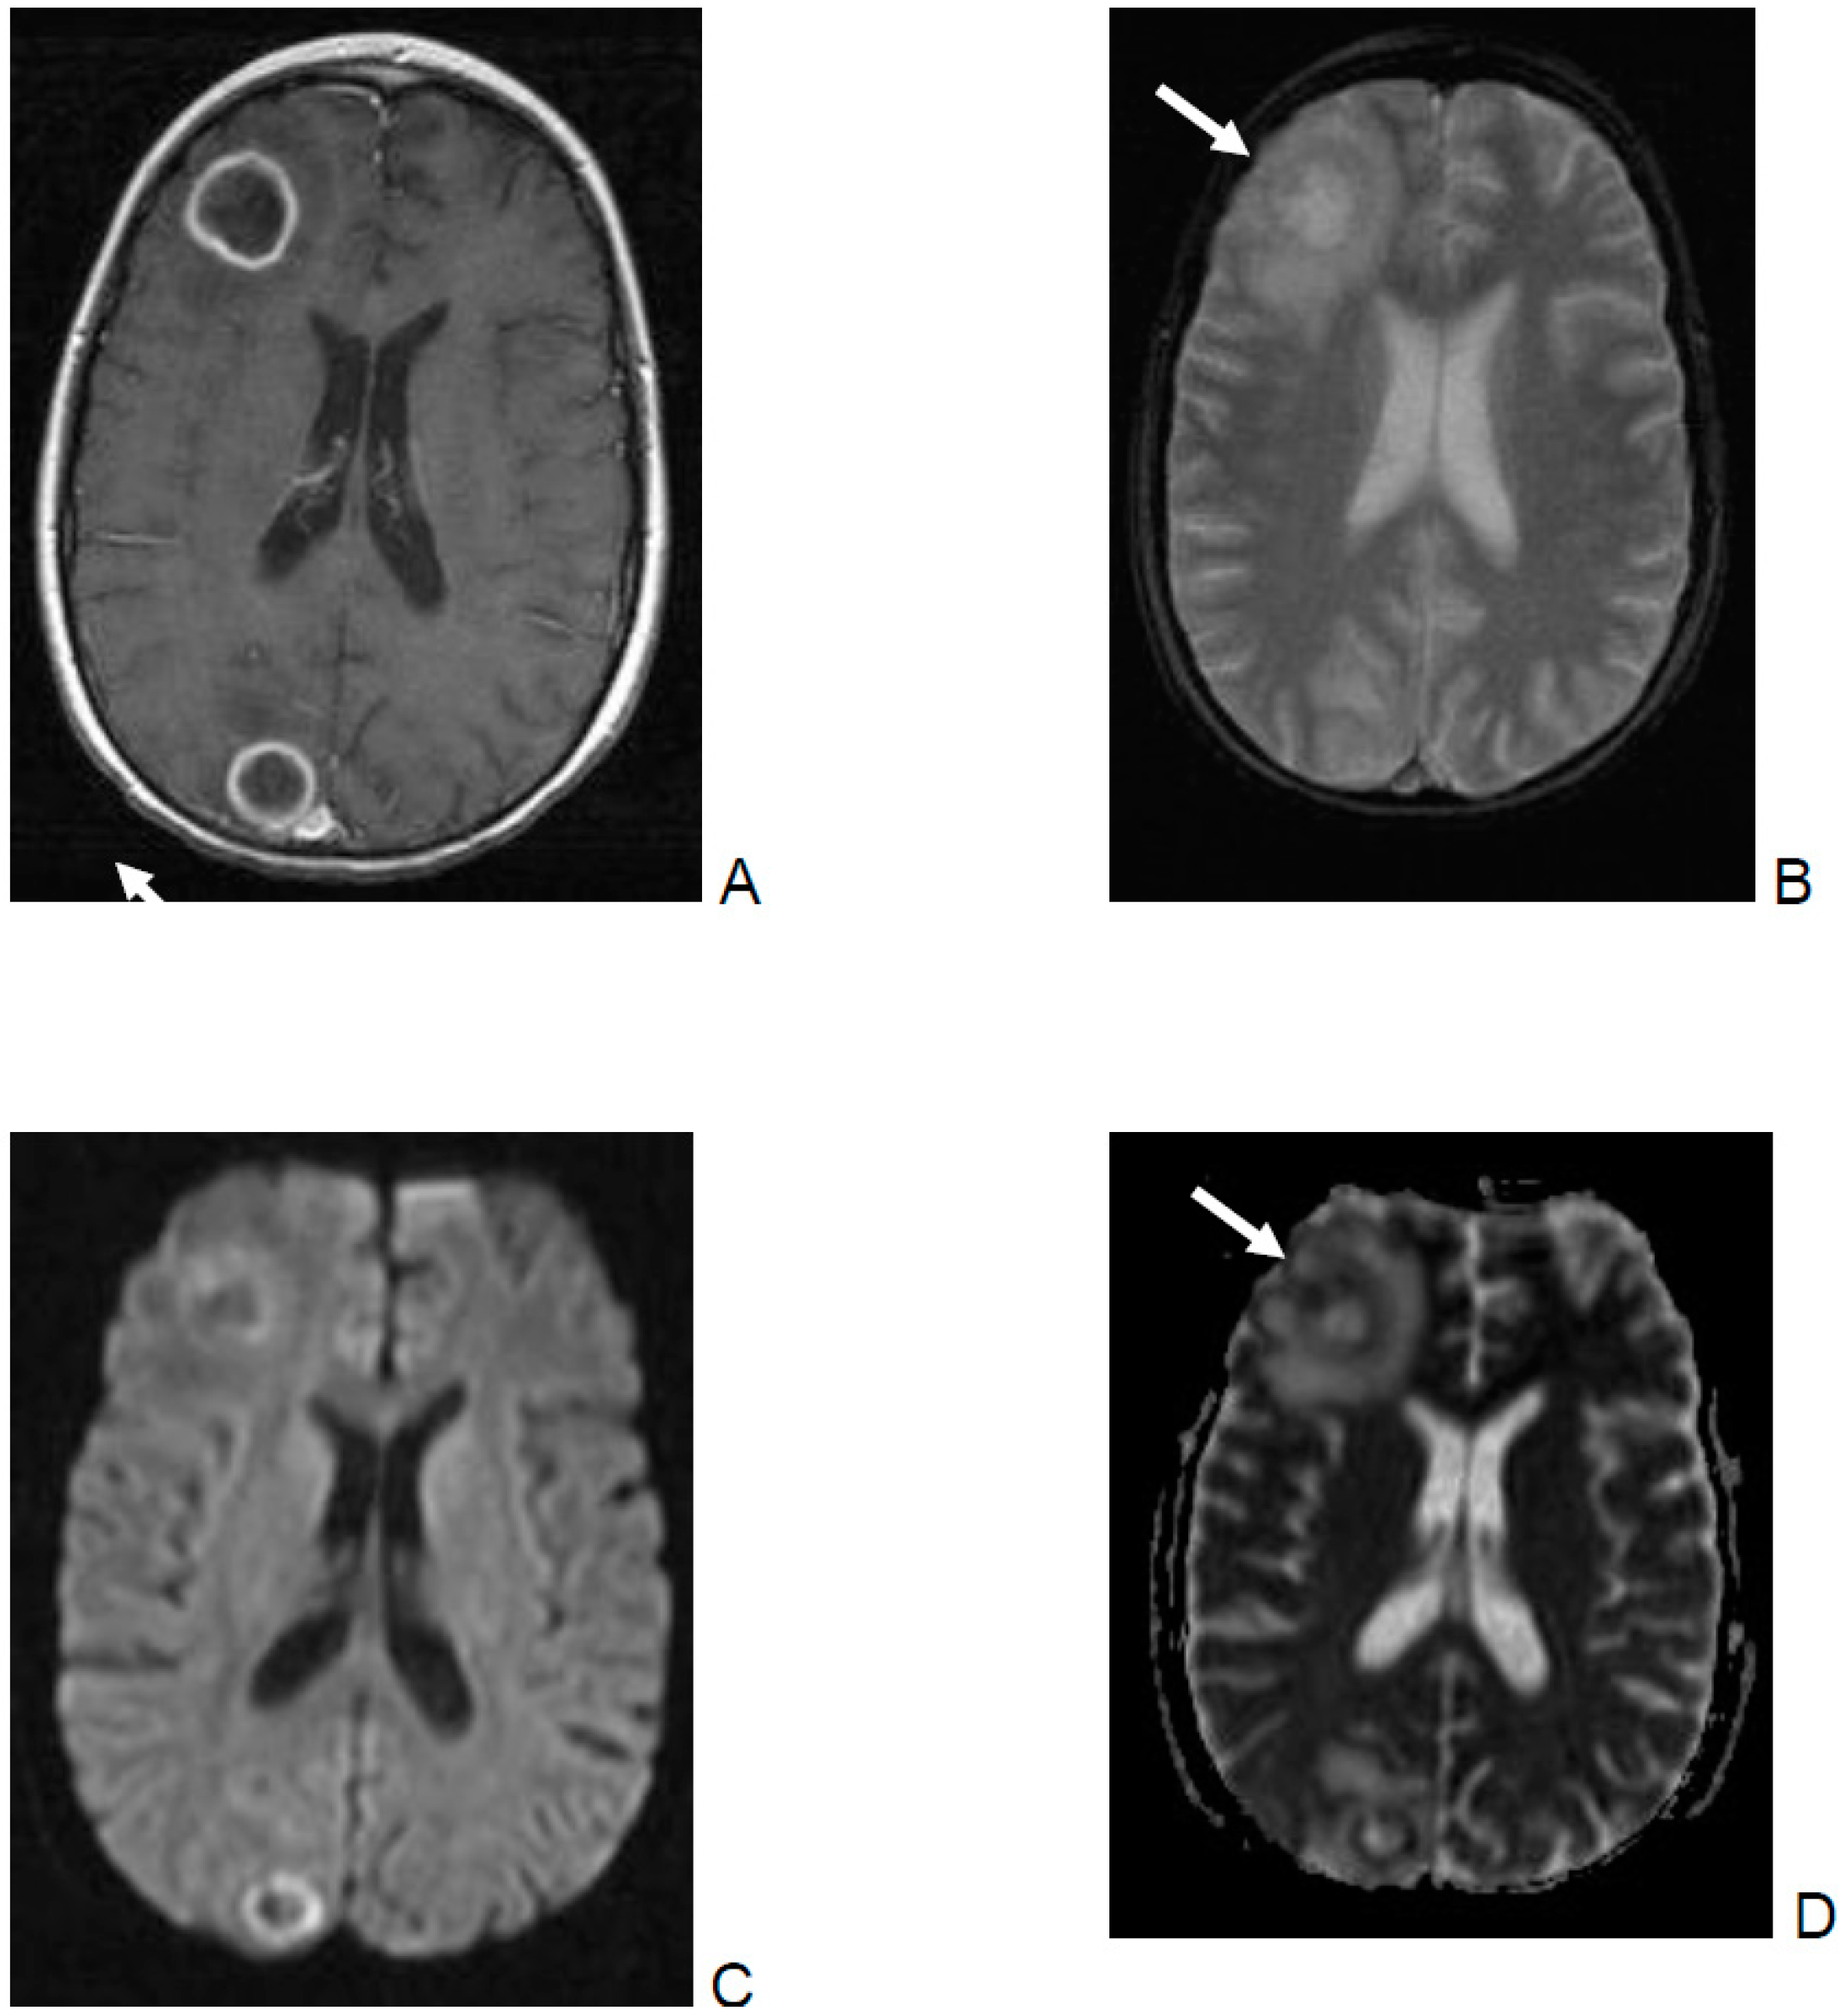

- DWI and ADC were evaluated for infarction, lesions with central restricted diffusion, lesions with a rim of restricted diffusion, and others. Infarction was defined as territorial, cortical, and sub-cortical lesions without nodular or ring-like aspect. Non-infarction-DWI restrictions, with nodular or ring-like aspect, were classified as lesions with central or rim-like restricted diffusion. Others included patients with cerebritis and bleeding.

- SWI/T2* were evaluated as follows:

- Parenchymal bleeding was defined as a hypointense parenchymal signal with “blooming”.

- Cluster of microbleeding was defined as a significantly hypointense cluster signal.

- Perivascular microbleeding was defined as a significantly hypointense perivascular signal.

- Ring-like was defined as a hypointense ring-like signal.

- Vascular blooming was defined as a vascular structure with signal loss and prominent “blooming” on SWI/T2*w sequences.

- Focal or multifocal involvement as well as the type of enhancement on T1 images after contrast were evaluated.